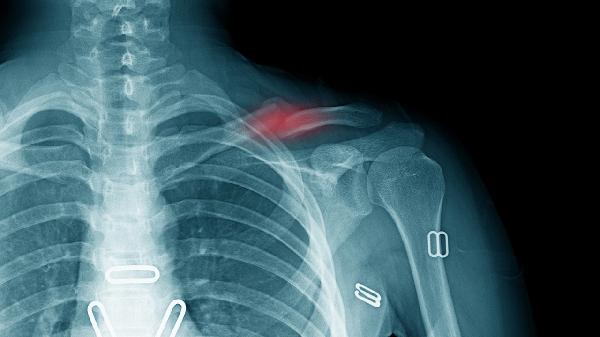

锁骨骨折可以不手术吗 锁骨骨折手术适应症和禁忌症剖析

锁骨骨折是否需手术取决于骨折类型和严重程度,部分稳定性骨折可保守治疗,但移位性骨折或合并神经血管损伤通常需手术干预。

无明显移位的锁骨中段骨折或儿童青枝骨折可采用八字绷带固定等保守治疗。这类情况骨折端稳定性较好,通过限制肩关节活动可促进自然愈合,一般4-8周可形成骨痂。保守治疗期间需定期复查X线片观察对位情况,同时配合康复训练预防肩关节僵硬。但保守治疗存在畸形愈合概率,可能影响后期肩关节活动范围。